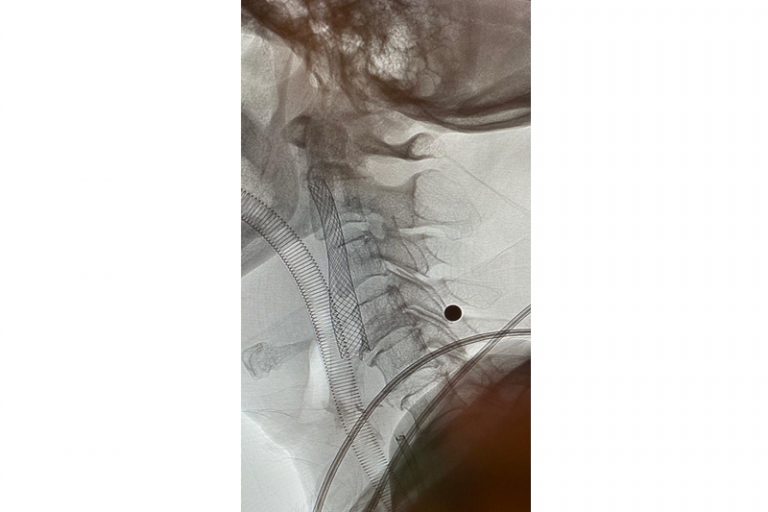

圖:導管遊走到病人右邊的頸和腦部血管大動脈,進行機械式血栓吸取

羅先生被送往私家醫院的第一步是進行緊急磁力共振造影,報告顯示羅先生右邊頸和腦部血管大動脈全部都被血栓堵塞着,右邊大腦缺血水腫,導致左邊手腳冇力和神智半昏迷。經過腦血管外科醫生的診斷和急救,在全身麻醉下,醫生使用尤如髪絲微細的導管,經過病人右邊大腿的腹股溝的大動脈而入,導管再經過腹部和胸腔的大動脈一直向上,遊走到病人右邊的頸和腦部血管大動脈,進行機械式血栓吸取內血管治療急救。

圖:血栓被吸取後,發現右頸內動脈血管嚴重狹窄是中風的主要原因。

圖:醫生植入血管支架來重新擴張狹窄的血管,以防止將來中風復發。